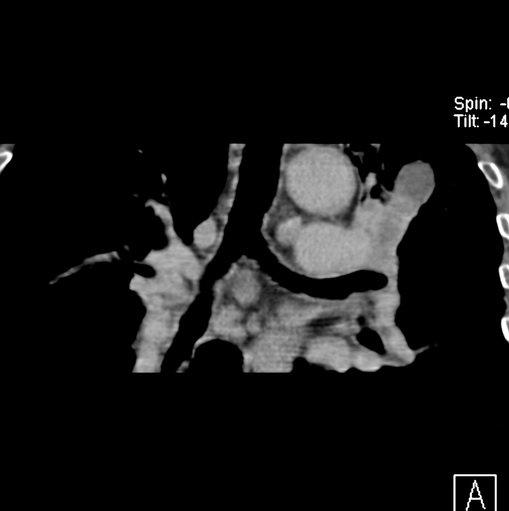

男性患者 81岁 咳嗽 咳痰 咯血

肿块贴近左肺门,包绕左上肺动脉,形态不规则。肿块增强扫描中度强化。纵膈内主动脉弓左旁间隙、气管隆突前、下间隙见多枚淋巴结影。综上考虑左侧中央型肺癌可能性大。图片没有完整上传,尤其是左肺上叶支气管分支层面没有上传,因此不好判断是叶支气管中断还是段支气管中断。另外,下图红色部分所示是“黏液支气管征”吗?